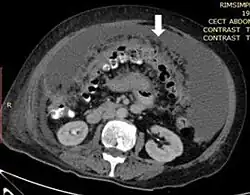

L'imagerie joue également un rôle clé dans la détection de la carcinose, l'évaluation de l'atteinte et la surveillance. Les modalités les plus performantes sont le scanner, l'IRM et le TEP scanner[9].